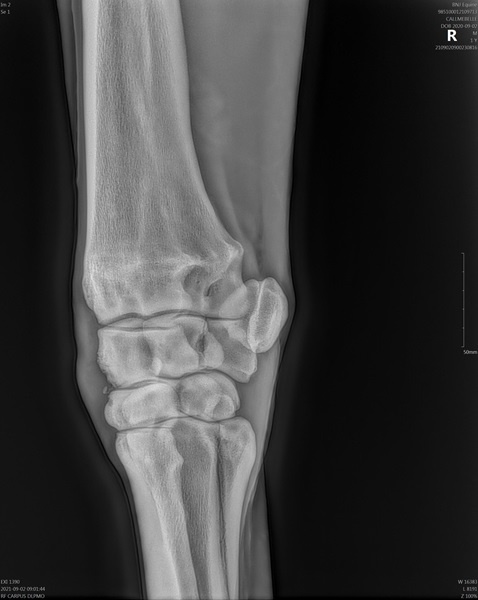

Mare (Belle) ceased racing due to injury (chip on offside knee) refer attached Veterinary Report. This mare won her race with this injury, which further demonstrates her determination and toughness.